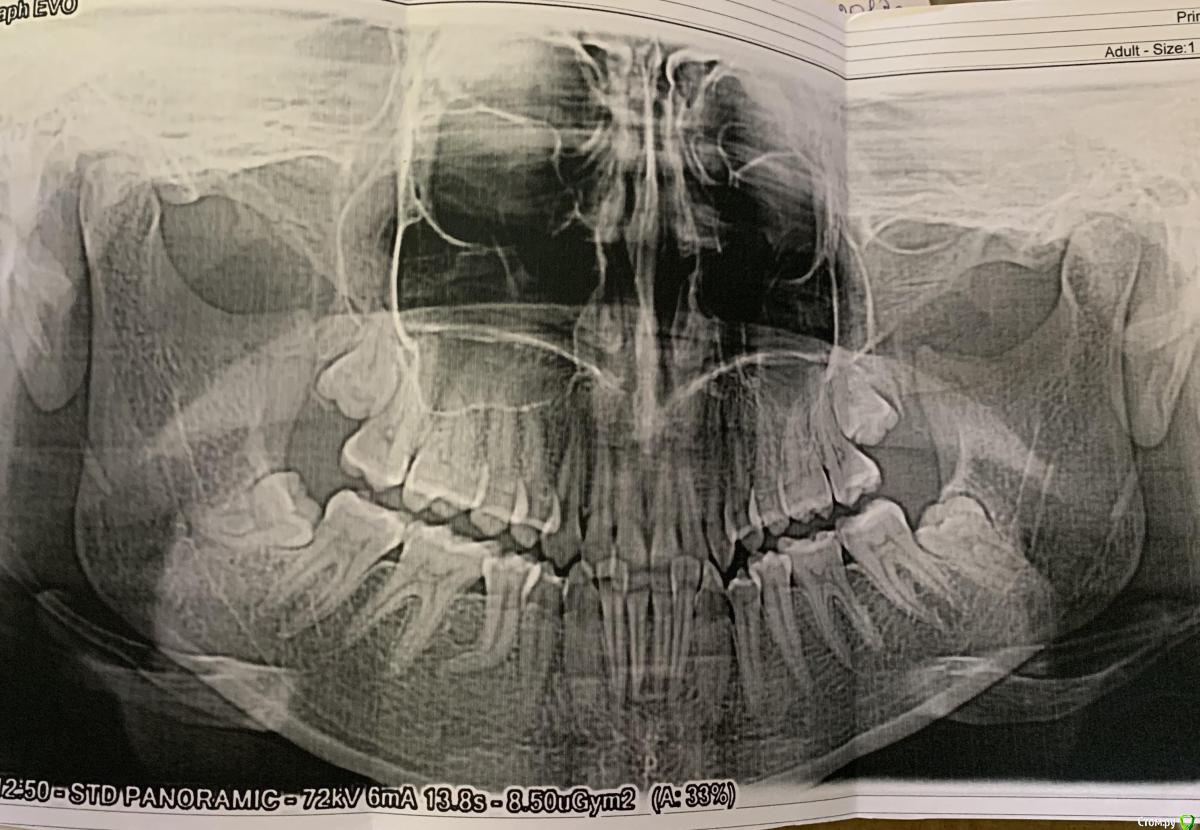

marionn Опубликовано 10 февраля, 2020 Поделиться Опубликовано 10 февраля, 2020 Добрый день, женщина, 31 годЧто беспокоит: на настоящий момент у меня ничего не болит. но на протяжении уже лет 5-6 в течение трех месяцев на внутренней поверхности передних нижних зубов образовывается зубной камень, каждый год посещаю стоматолога, и вот уже три года подряд мой стоматолог говорит, что мне необходима обязательная установка брекетов, ввиду того, что зубы стоят слишком скученно, что может привести к пародонтозу (или пародонтиту, не уверена в точности передаваемого) и что кариес на зубах, которых в основном образовывается в местах соприкосновения зубов друг с другом, возникает из-за прикуса. Также мой стоматолог сказала, что верхние зубы давят на нижние, а нижние на верхние из-за неправильного прикуса и таким образом еще больше деформируется челюсть, прикус и так далее. В настоящий момент у меня имеется панорамный снимок зубов, который я делала 2 года назад. Могли бы вы сказать, есть ли острая необходимость в брекетах и коррекции прикуса? Ссылка на комментарий